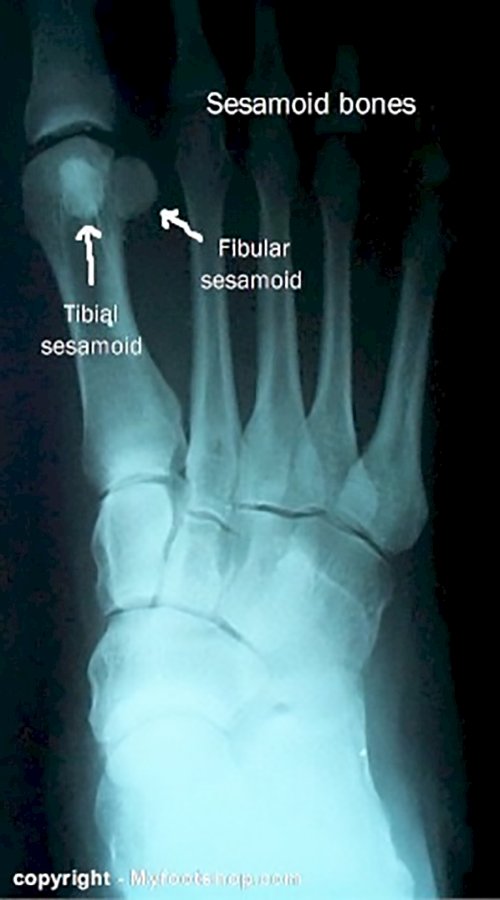

Sesamoditis is the term used to describe inflammation of a small bone in the foot known as the sesamoid bone. Each foot has a pair of sesamoid bones called the tibial (medial) or fibular sesamoid (lateral). The sesamoid bones act to facilitate the transfer of force around the bottom or plantar surface of the great toe joint. The sesamoid bones are incorporated within the tendon of the flexor hallucis brevis muscle. Sesamoid bones function much like the knee cap (patella), gliding over the surface of the joint, transferring mechanical load generated by a muscle.